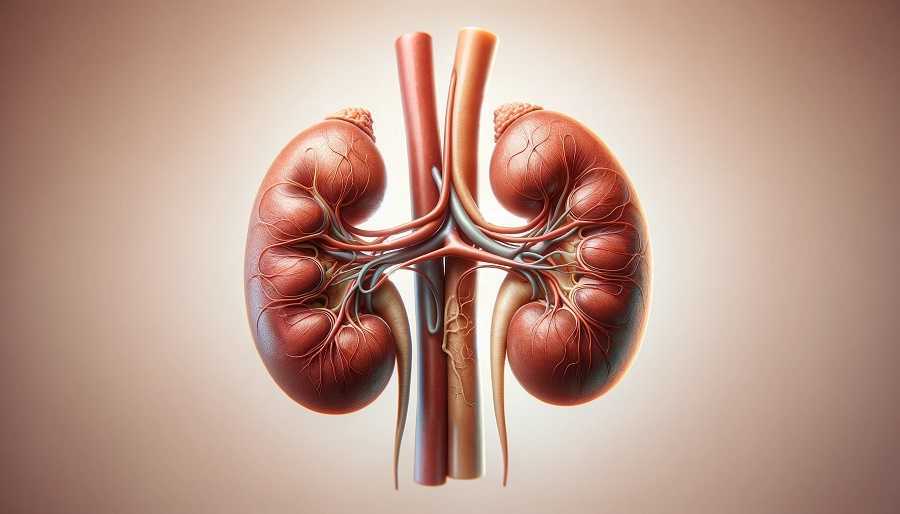

Primero, es importante saber qué hacen los riñones en nuestro cuerpo. Los riñones son órganos vitales que se encargan de filtrar la sangre y eliminar las toxinas y los desechos de nuestro cuerpo. Cuando los riñones no funcionan correctamente, estos desechos se acumulan y pueden causar graves problemas de salud. Por eso, es importante hacer exámenes de control periódicos, especialmente si se tienen antecedentes familiares de enfermedad renal.